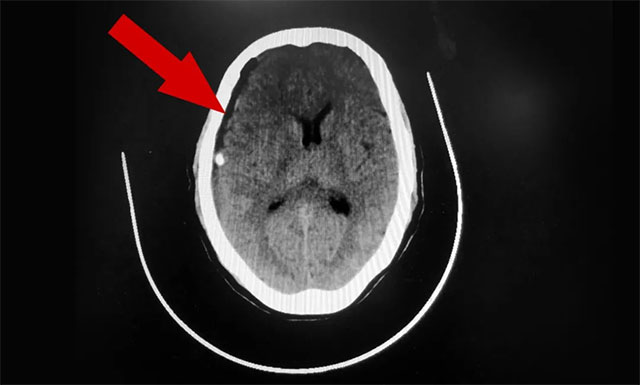

▲ 术后,患者硬膜下血肿已被引流清除